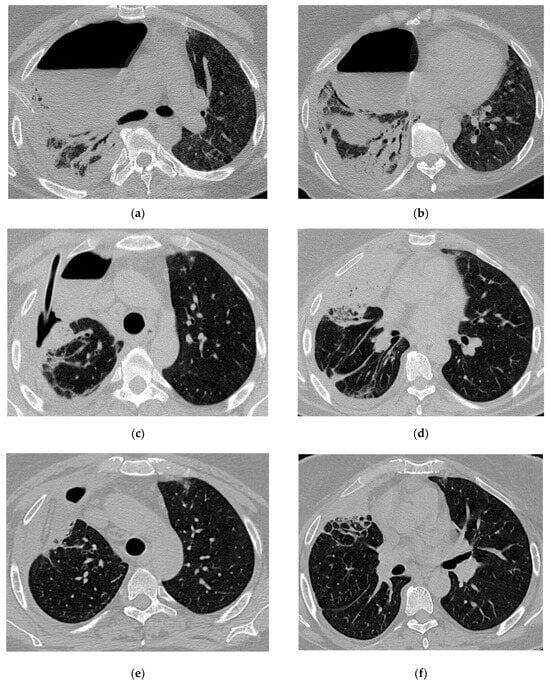

Figure 5.

Radiologic evolution of case 3: Axial chest CT scans after first percutaneous ICD insertion revealing insufficient drainage of the purulent cavity; pleural effusion with few air inclusions; right ICD and diffuse interstitial infiltrates (a,b). In this case, multiple drainage and drain revisions were necessary to optimally control the purulent infection. Smaller right residual cavity with stable pleural effusion after ICD revision (c,d). Chest CT scans 1-month follow-up show the Foley catheter and decreasing size of the residual cavity (e). A follow-up CT scan after ICD removal showed small residual pleural and pulmonary fibrotic changes (f).